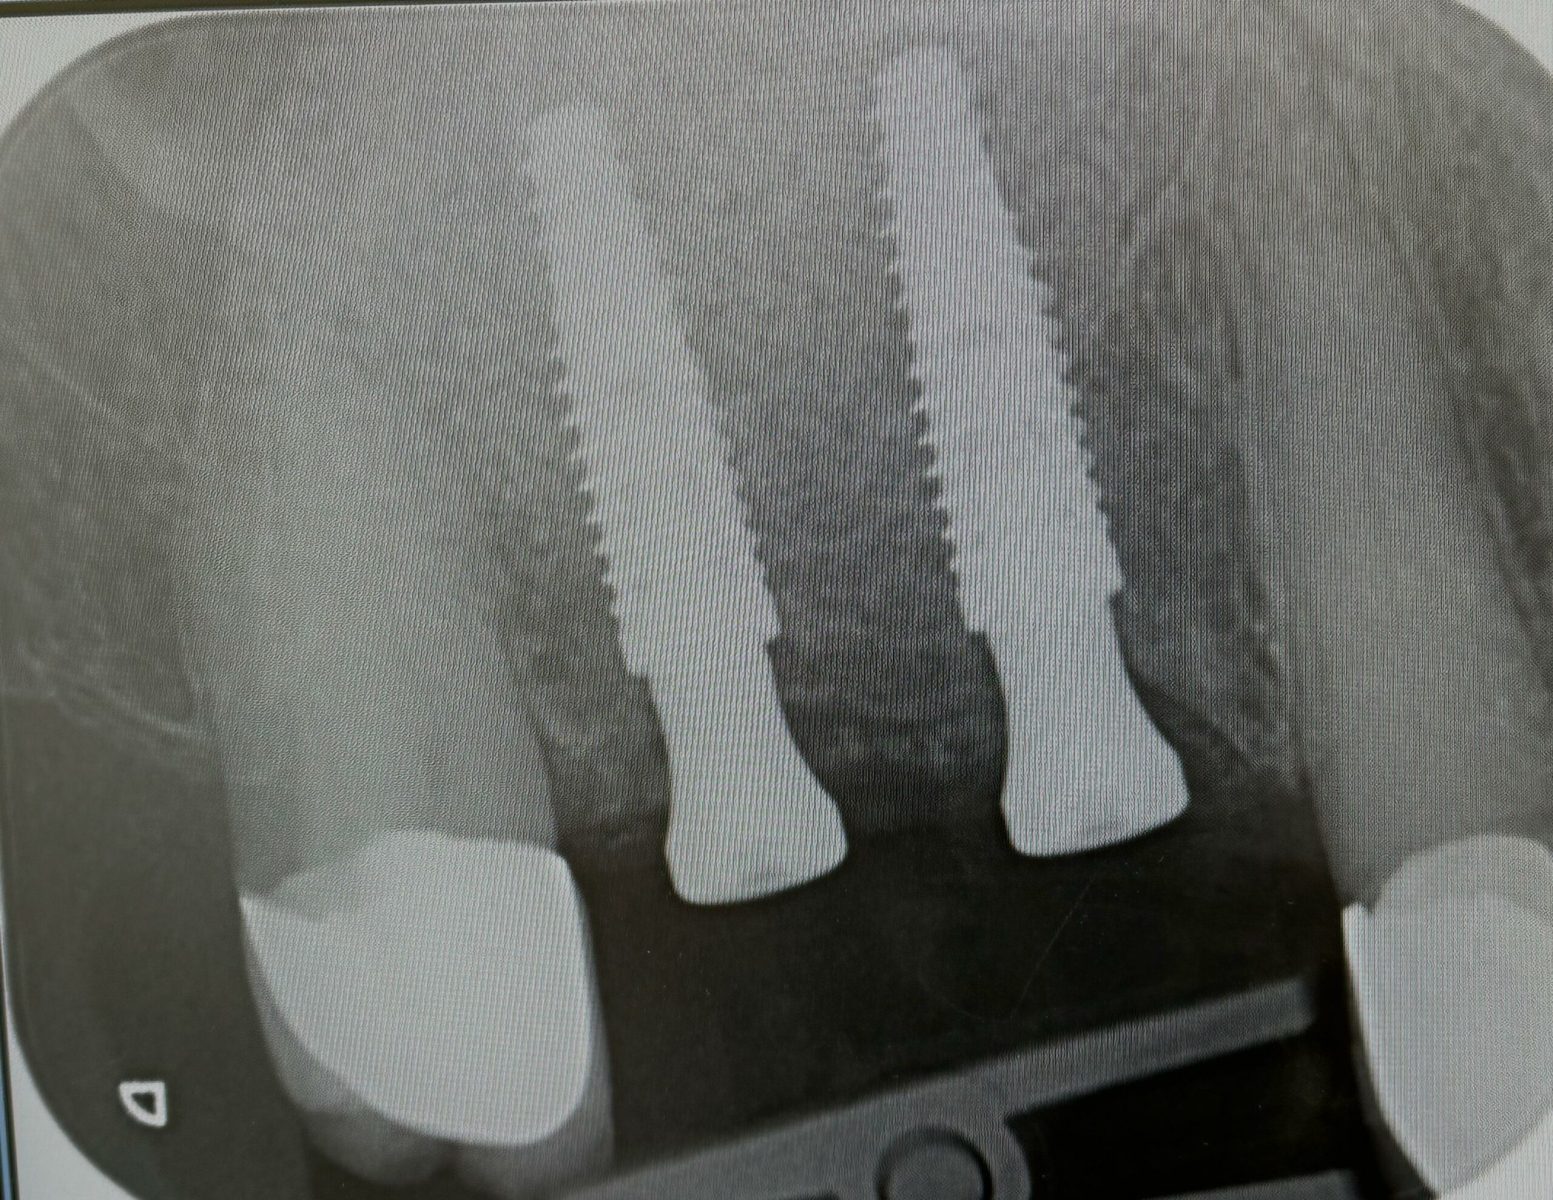

Implants placed using a digitally planned stackable surgical guide following alveolectomy, ensuring ideal positioning and a stable foundation for full-arch restoration.

Single implant case in the anterior region, following digital planning to ensure precise positioning and optimal aesthetic outcome. Pre-operative CBCT analysis was used to assess bone volume and guide implant angulation, allowing for a prosthetically driven approach.

The implant was placed with careful attention to surrounding anatomical structures and soft tissue preservation. This allowed for stable integration and proper support of the final restoration. Healing was uneventful, with good tissue response and maintenance of gingival architecture.